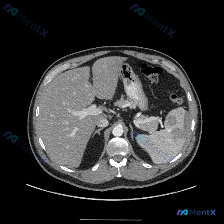

整理了一份脾脏多发低密度灶的CT读片和分析思路,这个病例其实很容易被“边界清”带偏,先把关键信息和我的思考过程放出来: 影像核心发现 单张上腹部CT横断面(软组织窗): - 肝脏、腹主动脉、下腔静脉等周围结构大致正常 - 脾脏实质内见数个类圆形低密度灶,边界相对清晰 - 无明显渗出、炎症或肿大淋巴结...